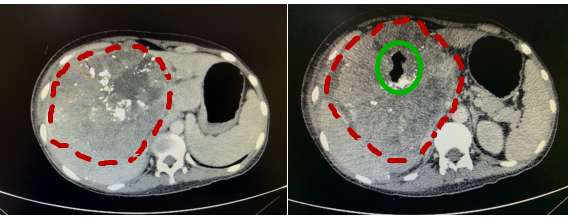

巨大肝肿瘤被完整切除